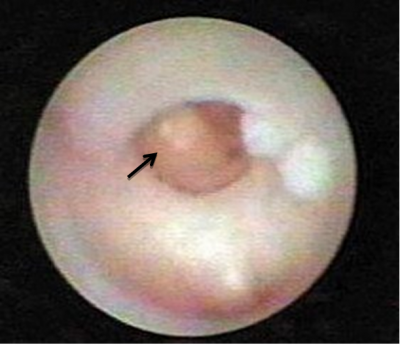

האבחנה מתבססת על הסיפור הקליני והבדיקה. ב-US אפשר להדגים צינורות מורחבים כביטוי לדוקטאקטזיה או אף לראות את הפפילומה (תצלום 16.12).

הדוקטוסקופיה החליפה את הדוקטוגרפיה במקומות בהם קיים הציוד המתאים לכך. בעזרת הדוקטוגרפיה אפשר להסתכל לתוך הצינורית, לזהות פתולוגיות ולדגום אותן (תמונה 4.12א').